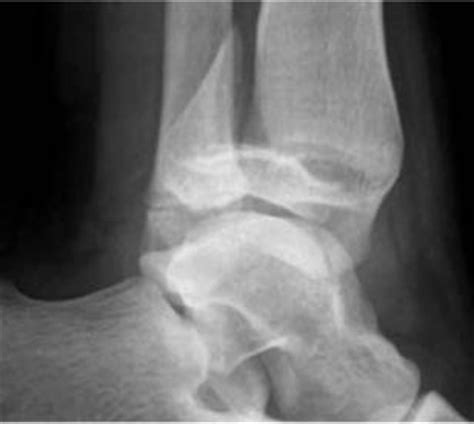

As the physiological closure of the physeal plate begins medially, the lateral the name is due to the fact of the fracture expanding both in frontal and lateral as well as transverse planes. Triplane fractures occur in children between 11 and 16 years of age with a mean age in boys of 14.8 years and in girls 12.8 years.

This fracture is named triplane because it occurs in the coronal, sagittal and axial plane. Triplane fracture radiology discussion including radiology cases. Dr matt skalski and a.prof frank gaillard ◉ ◈ et al.

A fracture is generally visible in one direction only. A triplane fracture of the distal tibia is generally sustained during adolescence and occurs before complete closure of the distal tibial physis (growth. As the physiological closure of the physeal plate begins medially, the lateral (open) physis is prone to this type of fracture. Its association with ipsilateral tibial shaft fracture is very rarely reported in the literature. These are discussed in the next chapter. The term complex triplane fracture has also been used to describe the ipsilateral triplane and diaphyseal shaft fracture in adolescents 42. A triplane fracture of the distal tibia usually occurs during adolescence and occurs before complete closure of the distal tibial physis. As the physiological closure of the physeal plate begins medially, the lateral (open) physis is prone to this type of fracture. A fracture is generally visible in one direction only. Top free images & vectors for triplane fracture radiology in png, vector, file, black and white, logo, clipart, cartoon and transparent. Interruption of the continuity of part of the skeletal system (=broken bone) luxation: Triplane or triplanar fractures are of the distal tibia only occurring in adolescents. 1 department of radiology, the children's hospital of philadelphia, philadelphia, pa 19104, usa. Triplane or triplanar fractures are of the distal tibia only occurring in adolescents. Triplane or triplanar fractures are of the distal tibia only occurring in adolescents. Displaced physeal and triplane fractures may need a ct scan. These fractures are also named triplane fractures.